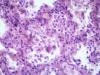

Подскажите как назвать данную пневмонию. По закону парных случаев, на данный момент у меня два разных случая с одинаковой морфологией. В морфологии в альвеолах эозинофильное содержимое, слущенные альвеолоциты, гигантские, многоядерные клетки, выраженный геморрагический компонент, местами немного лейкоцитов, свертки фибрина. Обширные свертки в бронхах. Очень похоже на вирусную, но как ее может назвать морфолог?

Интерстициально-десквамативная.

+ местами похоже на гиалиновые мембраны и в капиллярах межальвеолярных перегородок встречаются мегакариоциты.